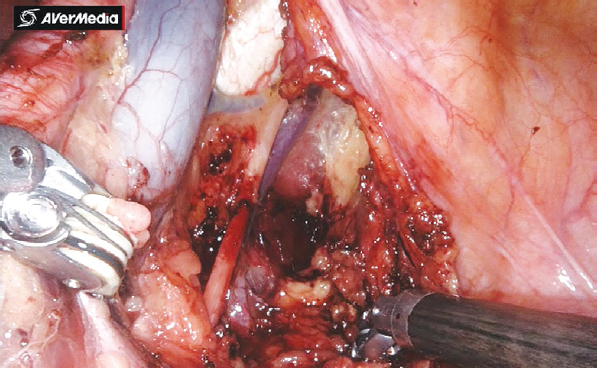

Рис. 2. Вид операционного поля после выполнения расширенной тазовой лимфаденэктомии

Рис. 3. Область запирательной ямки слева после лимфаденэктомии